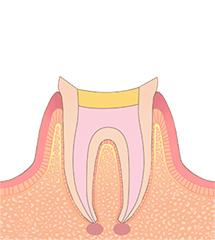

STEP06形成・印象

コアの型取りを行った場合、土台となるコアを取り付けてから、被せ物を作るために、歯の形を整え、再度型取りを行います。

可能な限り精密な型取りを行うことで、よりお口の中に合った被せ物を作ることができます。被せ物の作製は1週間ほどかかります。 -